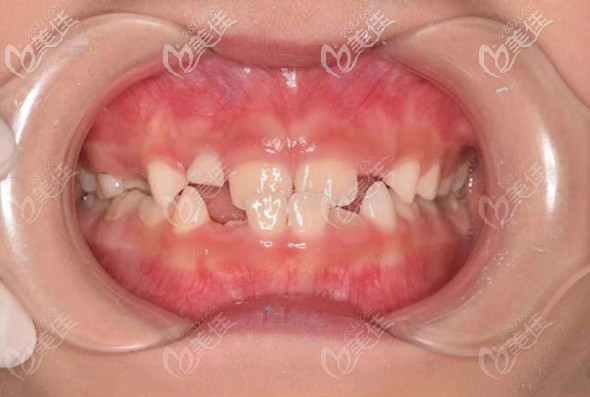

因為我自己結(jié)婚前也在北京朝陽區(qū)的瑞泰口腔醫(yī)院做過牙齒矯正,效果讓人很驚喜。所以,對孩子的牙齒也非常重視,在女兒6歲的時候,發(fā)現(xiàn)有“地包天”傾向,果斷帶孩子也來到瑞泰做兒牙矯治。

(這就是孩子的“地包天”牙齒造型 )

可能有些家長還不知道,這種牙齒癥狀的專業(yè)名叫反頜,是會影響孩子的咬合,也就是咀嚼食物的功能,重點是,發(fā)展下去,會導(dǎo)致臉型發(fā)育不好看。